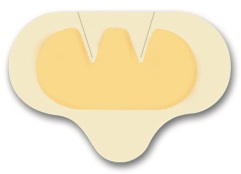

Pansamentul cu hidrocoloid Hydrocoll este recomandat in cazul ranilor si a escarelor neinfectate.

Hydrocoll este un pansament absorbant autoadeziv cu hidrocoloid, cu un strat superior semipermeabil, impermeabil pentru microorganisme si apa. Hidrocoloidul se transforma in gel la contactul cu exsudatul din plaga, formand un mediu umed cu efect stimulant asupra granulatiei si epitelizarii.

Caracteristici Pansament Hydrocoll:

• Pansament cu hidrocoloid, autoadeziv;

• Viteza si capacitate excelenta de absorbtie;

• Nu se lipeste de plaga;

• Este semipermeabil;

• Permite toaleta zilnica;

• Remanenta pe plaga este de 3 – 5, pana la 7 zile;